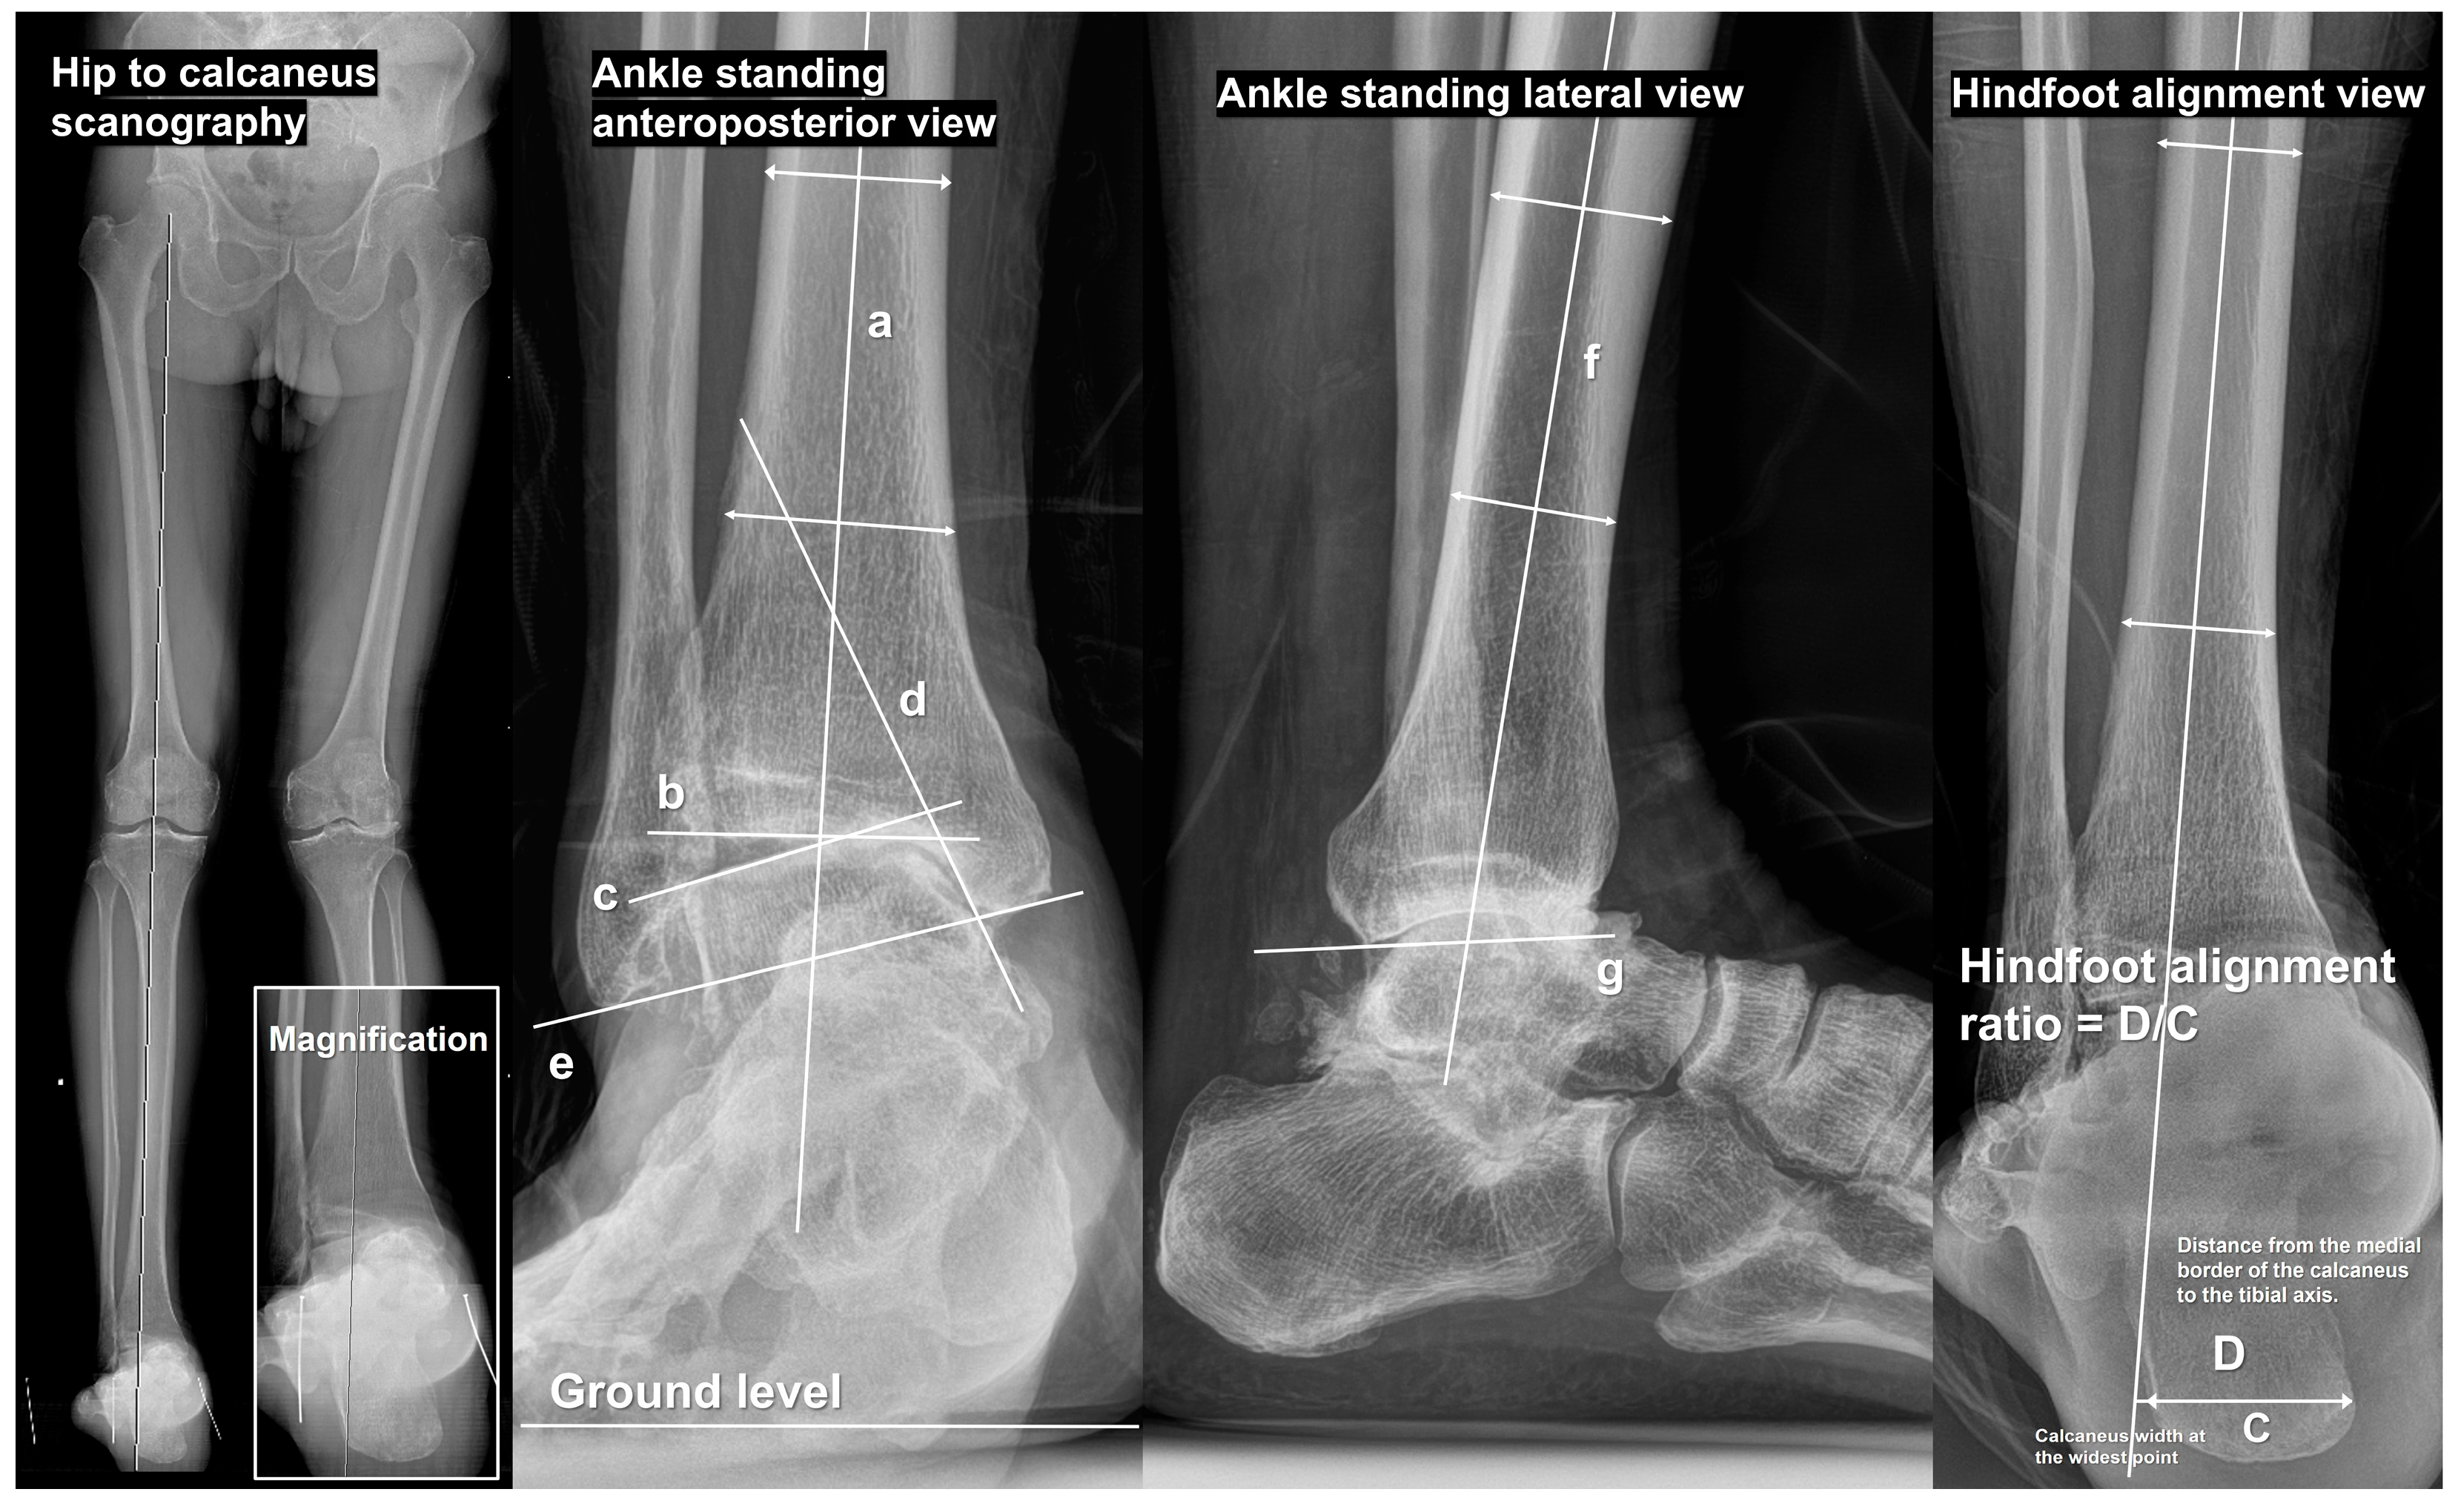

| Parameters | Clinical Implications | Reference Range |

|---|---|---|

| TAS | A quantitative measure of correction | 88–93° |

| TT | Aim of correction | ≤4° |

| TMMA | A quantitative measure of medial malleolar erosion | 20–25° |

| TCA | Relative fibular length measurement | 8–15° |

| TPI | Tibial plafond coronal alignment relative to the ground (a supplementary aim of correction) | N/A |

| TLS | Sagittal alignment parameter of the distal fragment after correction (anterior/posterior angulation) | 79–83° |

| HMA | A parameter assessing hindfoot alignment | Neutral alignment when the tibial bisecting line intersects the lowest point of the calcaneus |

| HAR | A parameter assessing hindfoot alignment | 0.3–0.5 |